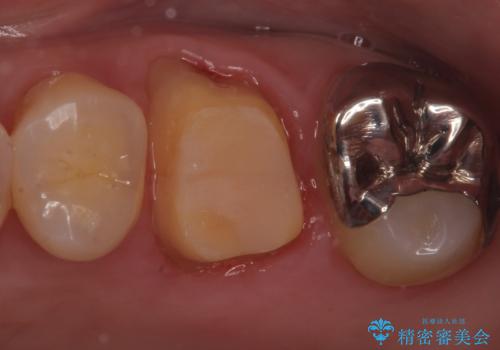

割れた被せ物を作りなおしたい

- 他院で装着した被せ物が割れたとのことで来院されました。

被せ物の厚みが確保されていなかったため、向かいの歯とのスペースを確保するように修正していきます。

被せ物の厚みが十分に確保できていないと、材料によっては今回のように割れてしまうことがあります。

被せ物の材料を変えるか、厚みを確保することでそのリスクを抑えることができます。

今回はセラミックでの再治療をご希望されたため被せ物の厚みを確保することで対応しました。